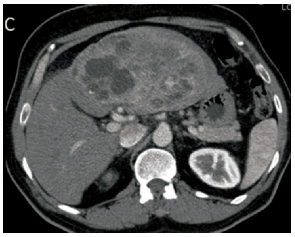

Paciente de 61 anos, sexo feminino, apresenta quadro de dor abdominal incaracterística há cerca de

2 meses, acompanhado de vermelhidão facial eventual, emagrecimento. O exame físico do abdome

parecia normal, com discreto aumento indolor do fígado. Sem sinais clínicos ou laboratoriais de icterícia.

Chega ao hospital já com propedêutica avançada, porém, ainda sem diagnóstico. Entre os exames,

há vários marcadores tumorais (CEA e CA 19-9 normais, cromogranina A elevada, e Ácido 5-Hidroxi

indolacético aumentado), enzimas hepáticas normais e uma tomografia computadorizada que gerou a

imagem abaixo:

Em relação a esse caso, o diagnóstico mais provável é